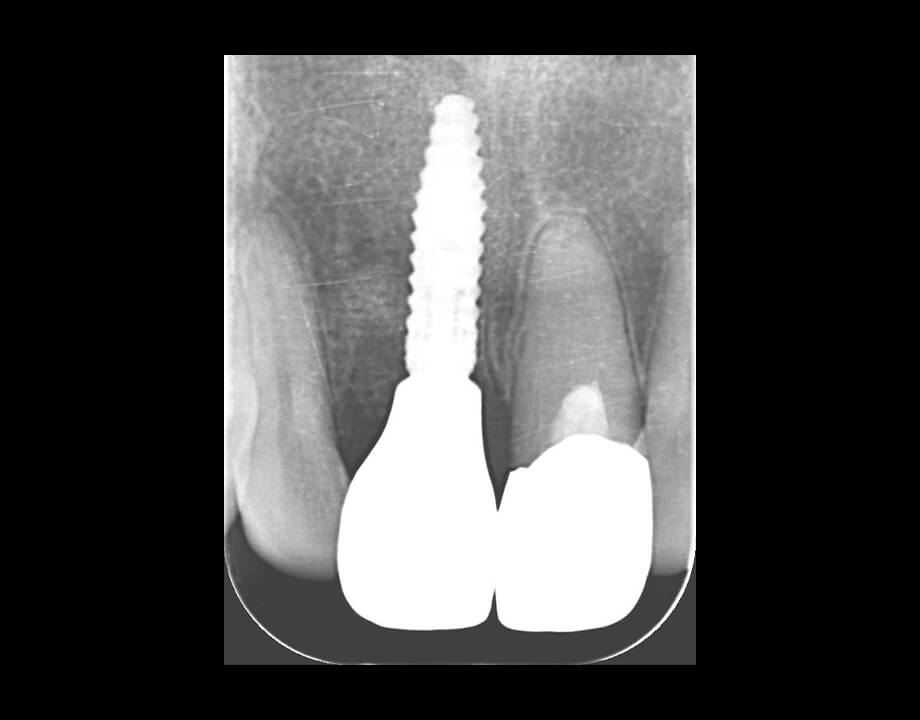

Case 02インプラント

モノリシックジルコニア